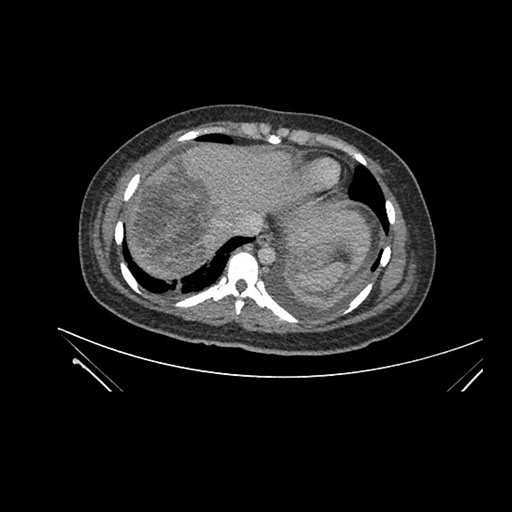

Axial Venous